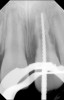

Fig 15. Preoperative radiograph.

Figure 15